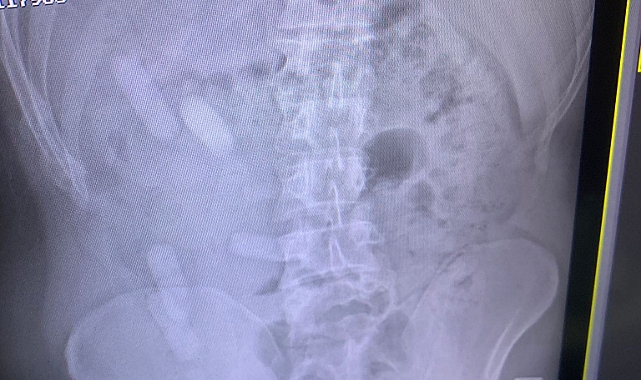

Edinilen bilgiye göre Sivas İl Jandarma Komutanlığı ekipleri, D-100 karayolu Yıldızeli ilçesi geçişinde Lasy isimli narkotik köpeği ile yol denetimi gerçekleştirdi. İranlı yolcuları taşıyan 84 AA 845 plakalı otobüste yapılan aramada A.E. (34) isimli şahsın üzerinde, içerisinde reçine esrar bulunan 140 kapsül ele geçirildi. Şüphe üzerine A.E. isimli İranlı şahsa çekilen röntgen filminde midesinde de 15 kapsül olduğu anlaşıldı.

Kapsüller doğal yollarda çıkartıldı. A.E. jandarma ifadesinin ardından çıkartıldığı adli makamlarca tutuklanarak cezaevine konuldu.